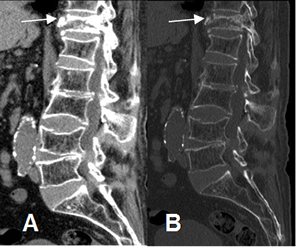

Fig 217. Fracturas.

A: TAC reconstrucción sagital en ventana de tejido y B: reconstrucción en osea. Signos de osteoporosis generalizada, con aplastamiento de D12 y alteración en las placas de L3 y L4.